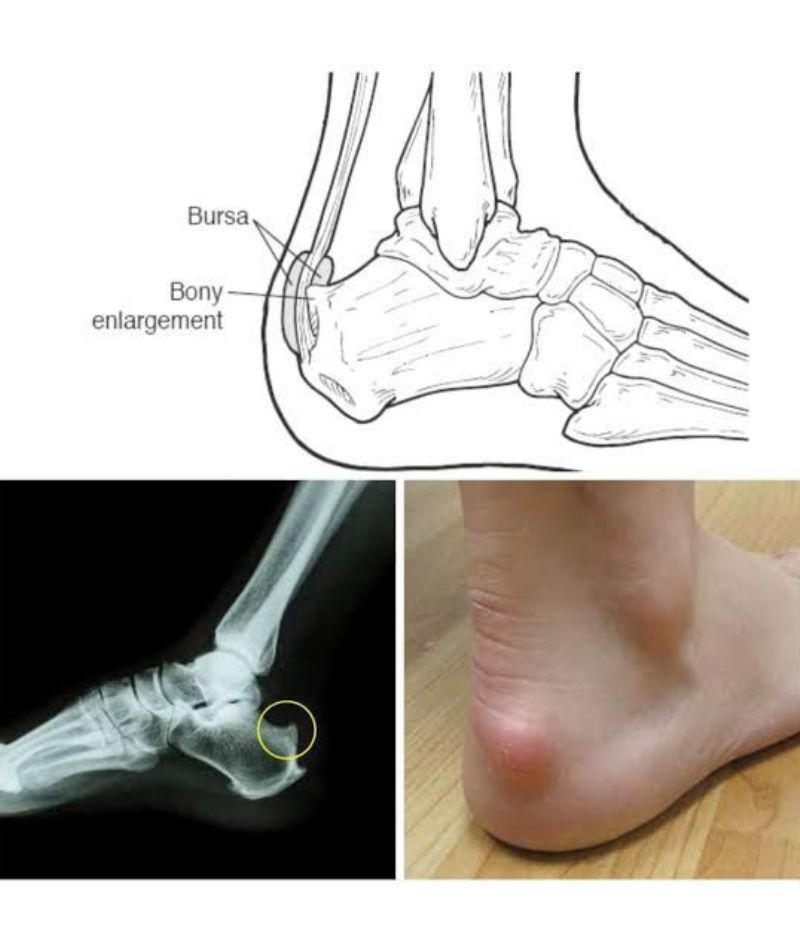

It is a hard bony enlargement which is situated at the back of the heel. There is a tendon known as tendo-achilies, which is important to raise the heel, situated between the enlargement and the skin. So, whenever the subject with this deformity wears hard back shoes, the enlargement runs against the soft tissues and the tendon which gives rise to micro trauma and tears. This gives rise to immense pain and swelling in this particular region and in the long run may lead to rupture. Diagnosis is made by history taking and physical examination as well as X-rays. The rupture can be detected by sonography and MRI. Mostly treated by conservative methods like heel pads and heel lifts, local ice application, stretching exercises and/or avoiding up heel tasks. When it is a chronic problem, it needs surgical intervention in the form of excision.